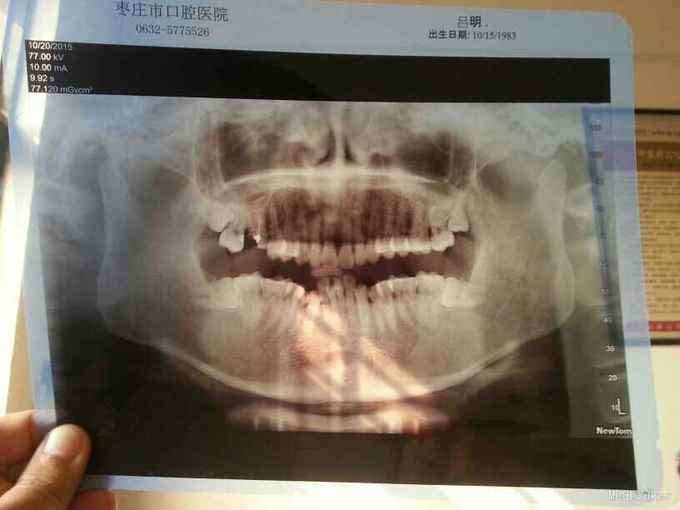

男 32岁 右上六深龋,根管治疗后行烤瓷牙修复,一月后塞牙严重,烤瓷牙去除后,行曲面断层拍摄,影像显示右上六远中大面积缺损,右上七远中倾斜,右上八阻生